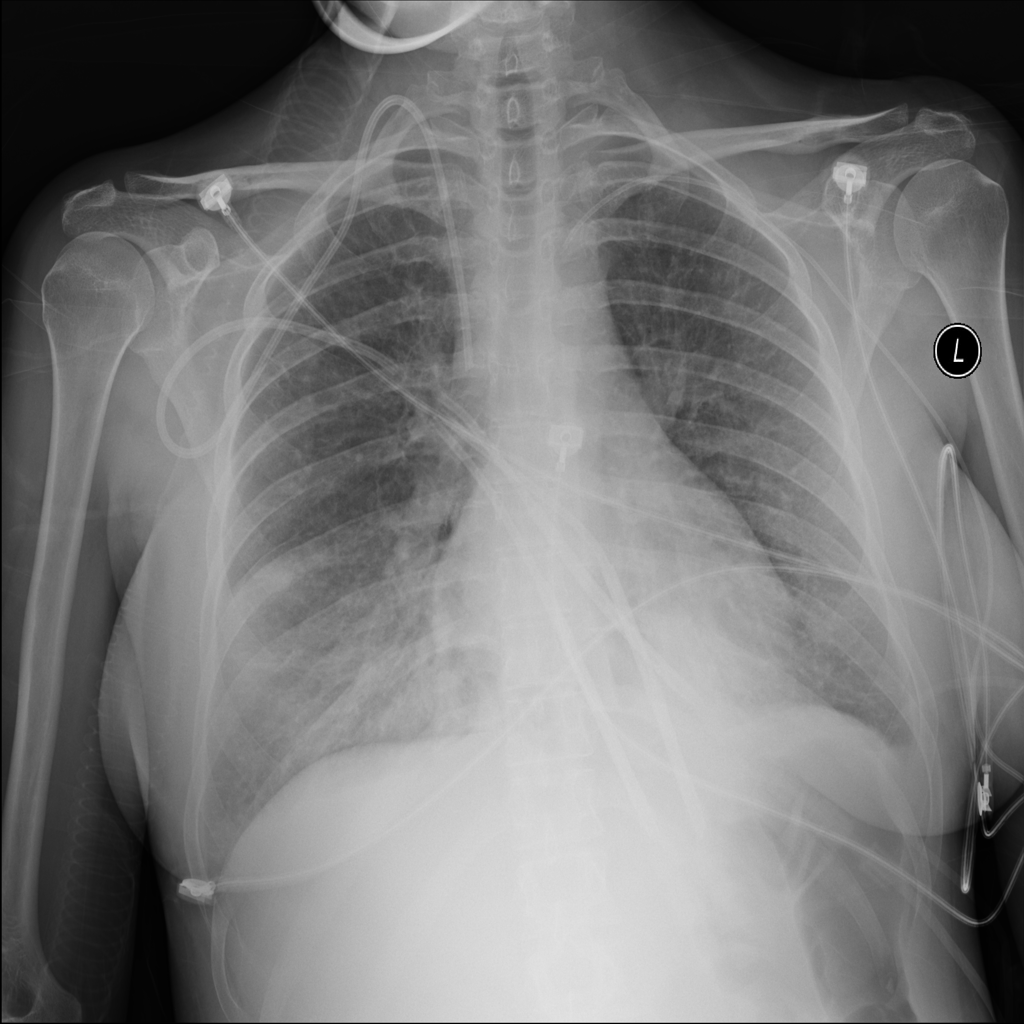

PAT-24D9 · IMG-006Edema

PAT-24D9 · IMG-006

AP